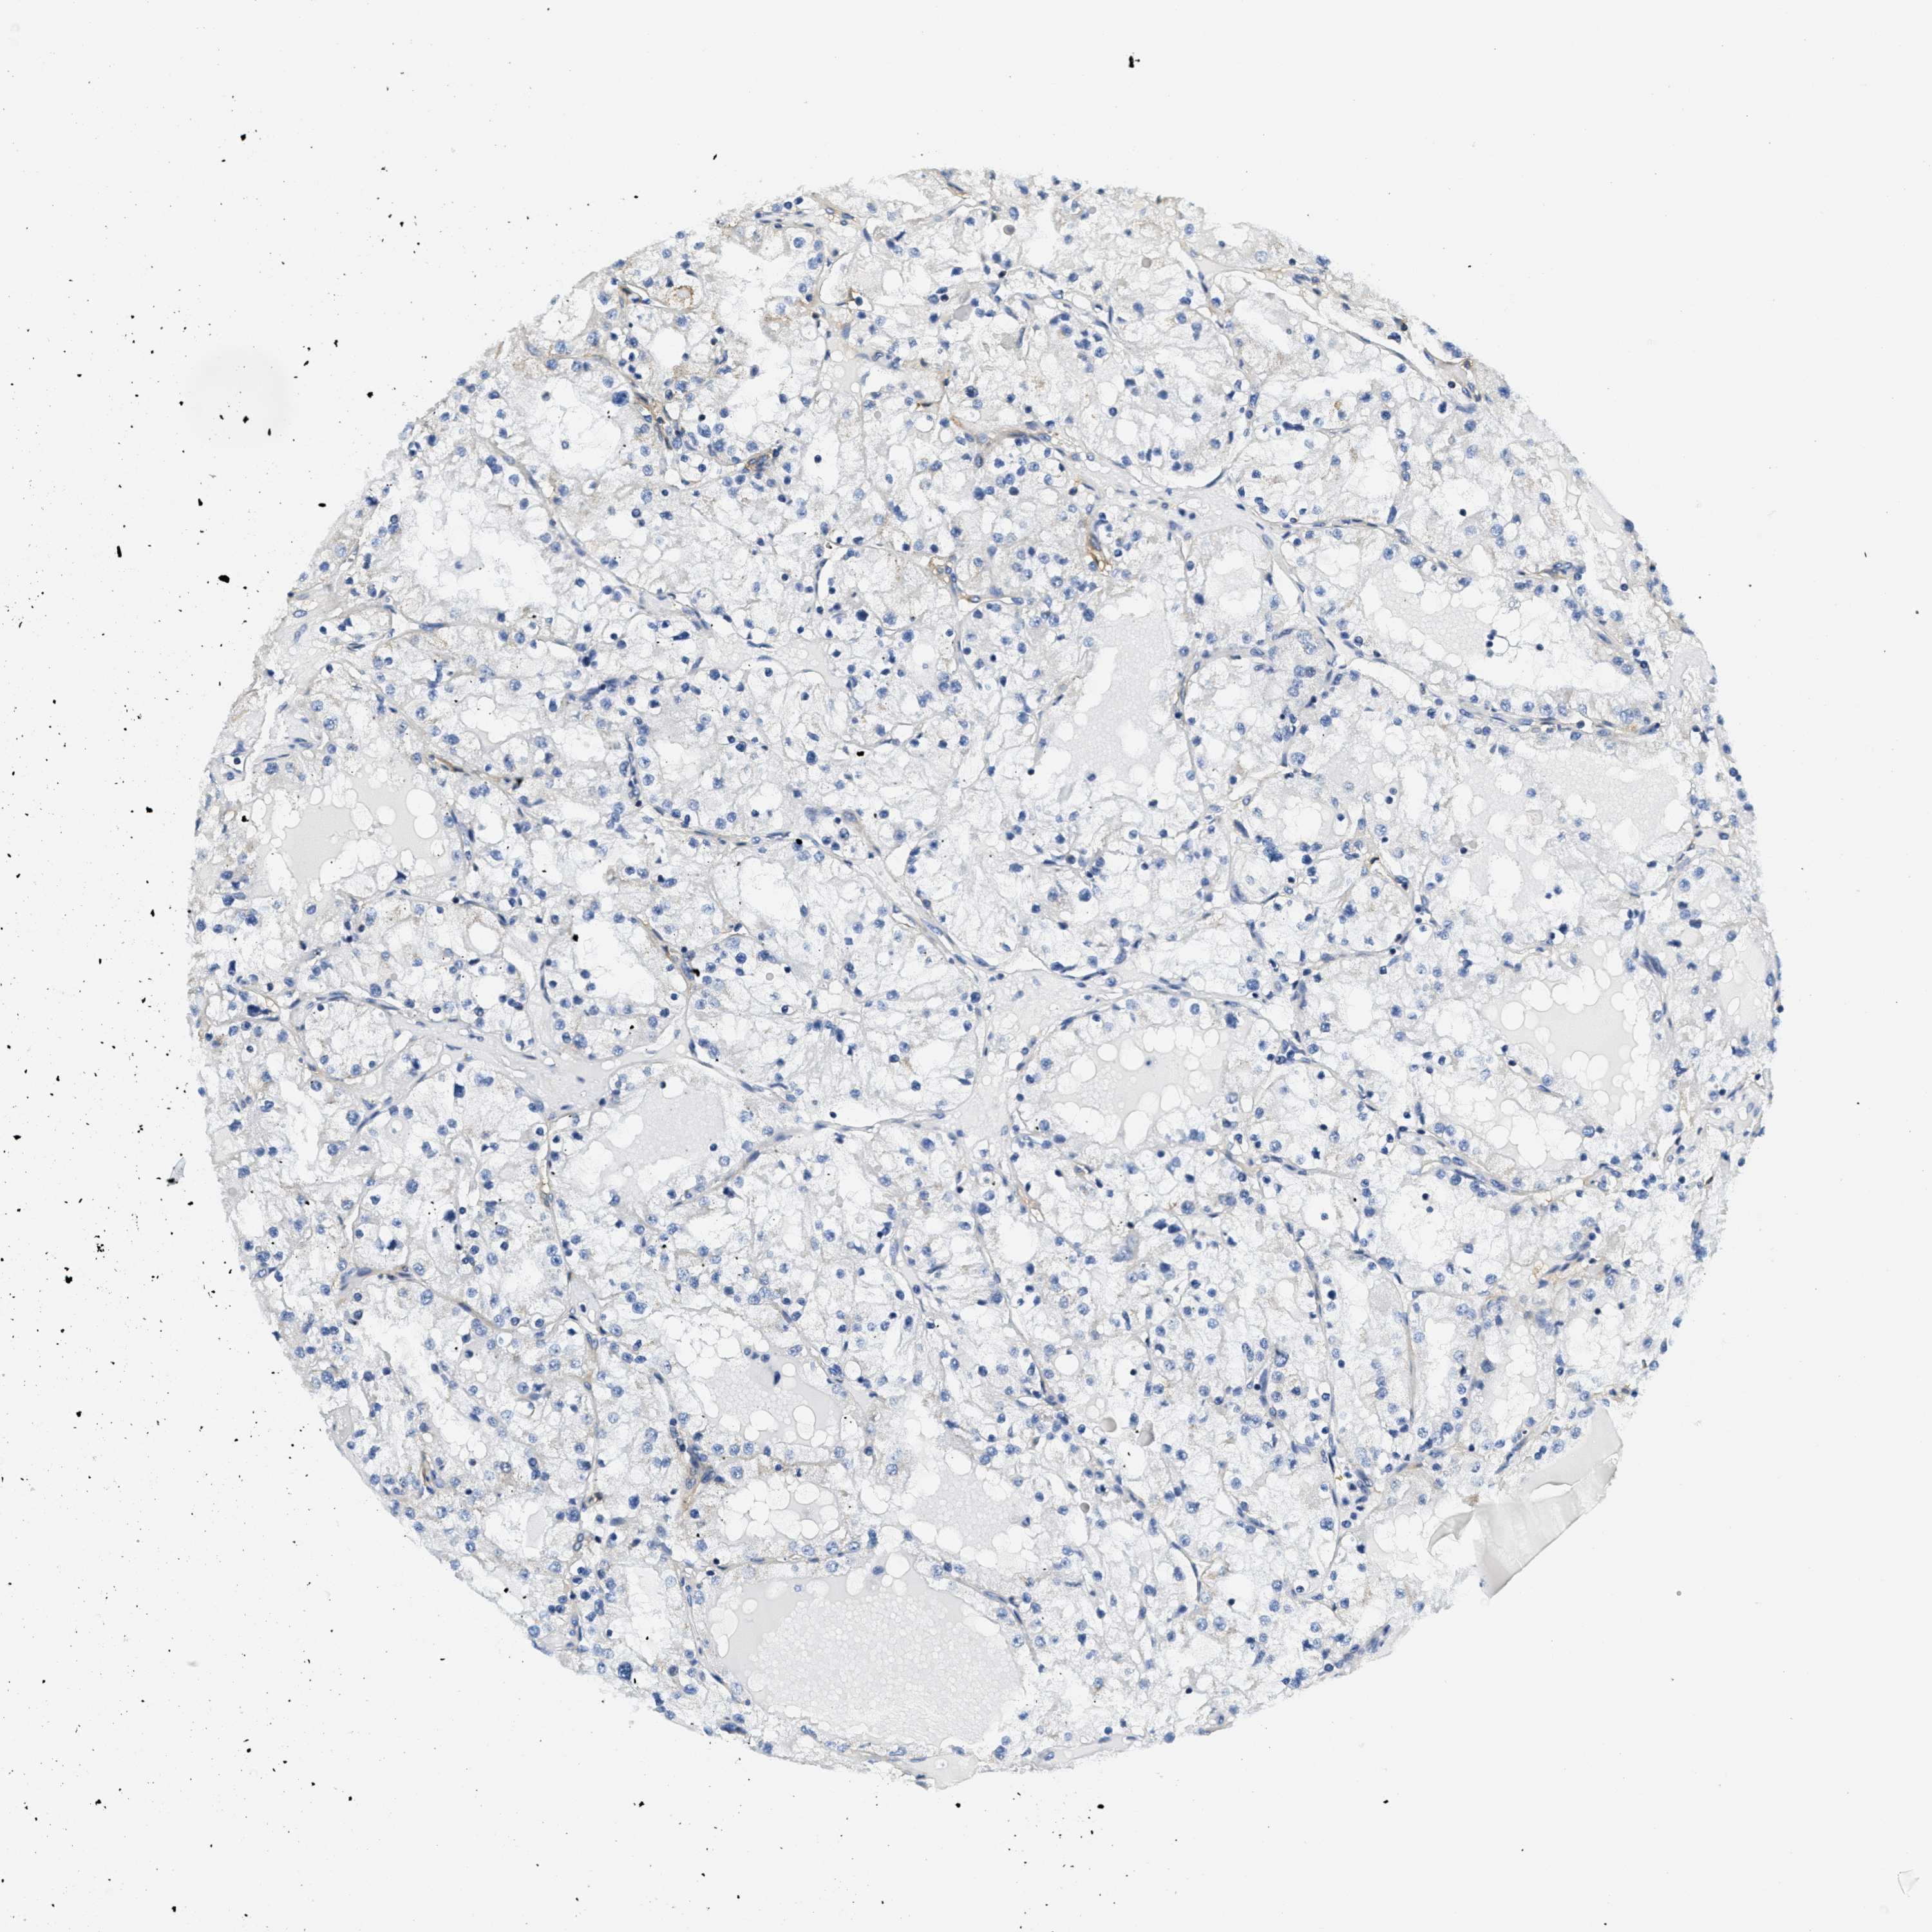

KIDNEY RENAL CLEAR CELL CARCINOMA (TCGA) - Interactive survival scatter ploti

The Survival Scatter plot shows the clinical status (i.e. dead or alive) for all individuals in the patient cohort, based on the same data that underlies the corresponding Kaplan-Meier plots. Patients that are alive at last time for follow-up are shown in blue and patients who have died during the study are shown in red.

The x-axis shows the expression levels (FPKM) of the investigated gene in the tumor tissue at the time of diagnosis. The y-axis shows the follow-up time after diagnosis (years). Both axes are complimented with kernel density curves demonstrating the data density over the axes. The top density plot shows the expression levels (FPKM) distribution among dead (red) and alive patients (blue). The right density plot shows the data density of the survived years of dead patients with high and low expression levels respectively, stratified using the cutoff indicated by the vertical dashed line through the Survival Scatter plot. This cutoff is automatically defined based on the FPKM cutoff that minimizes the p-score. The cutoff can be changed by dragging the vertical line or by entering a cutoff value in the square labeled "Current cut-off".

Under the Survival Scatter plot the p-score landscape (black curve; left axis) is shown together with dead median separation (red curve; right axis). Dead median separation is the difference in median mRNA expression between patients who have died with high and low expression, respectively. It is calculated as follows: median FPKM expression of dead patients with high expression - median FPKM expression of dead patients with low expression. This is intended to aid the user in visually exploring custom cutoffs and the associated p-scores and dead median separation.

Individual patient data is displayed and can be filtered by clicking on one or more of the category buttons on the top of the page. Categories describing expression level and patient information include: high, low, alive, dead, female, male and tumor stages. The scale of the x-axis can be toggled between linear and log-scale by clicking on the "x log" button. Mouse-over function shows TCGA ID, patient information and mRNA expression (FPKM) for each patient.

& Survival analysisi

Kaplan-Meier plots summarize results from analysis of correlation between mRNA expression level and patient survival. Patients were divided based on level of expression into one of the two groups "low" (under cut off) or "high" (over cut off). X-axis shows time for survival (years) and y-axis shows the probability of survival, where 1.0 corresponds to 100 percent.

CA4 is validated prognostic, high expression is favorable in Kidney Renal Clear Cell Carcinoma (TCGA)

: 3.04

Average pTPM 15.4

Number of samples 521